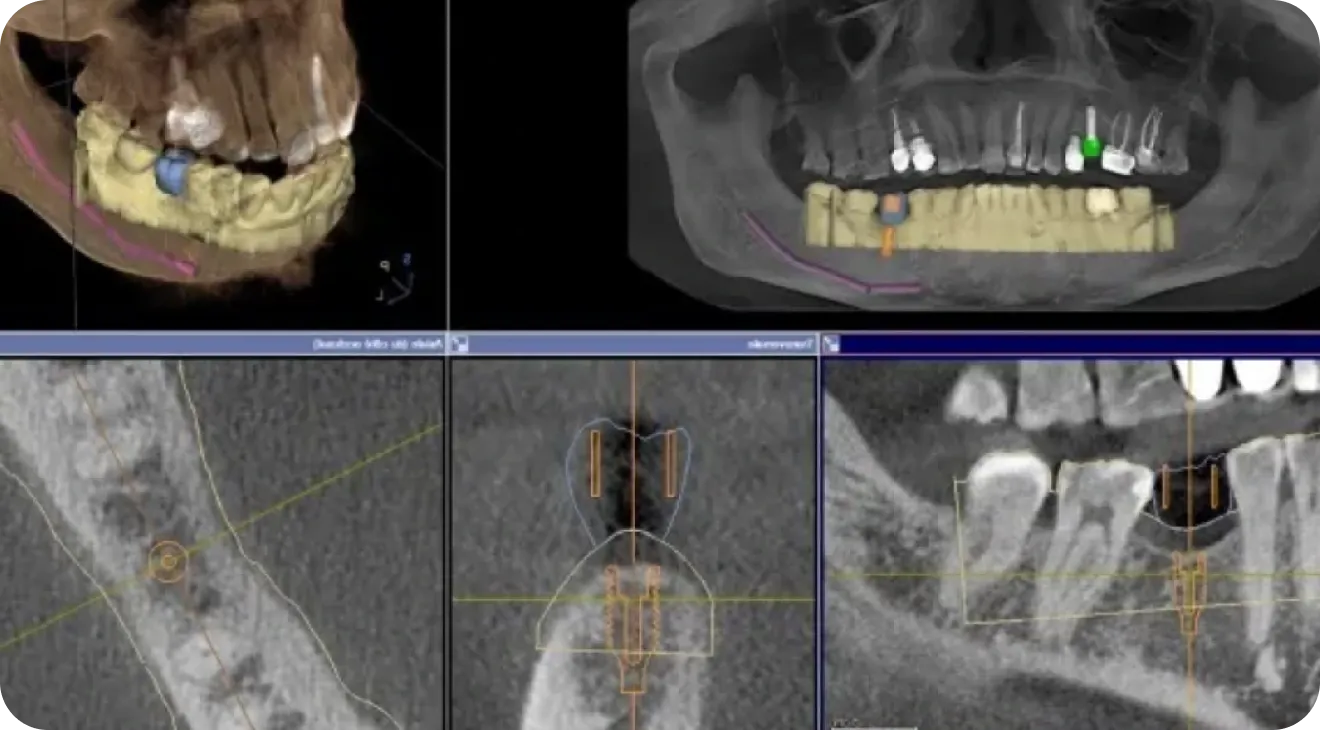

Radio panoramique 3D

La radiographie panoramique et 3D permet au praticien un expertise affinée et précise des tissus dentaires et maxillaires.

Permettant de diagnostiquer des pathologies de manière plus précise, permet une planification rigoureuse des chirurgiens reconstructrices et implantaires .